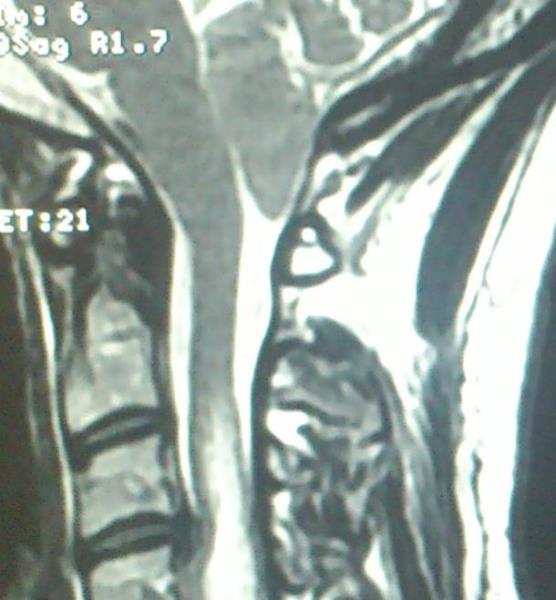

Ασθενής  γυναίκα 49 ετών προσήλθε λόγω υπινιακής κεφαλαλγίας εκλυόμενης και επιδεινούμενης  κατά την επίκυψη και  την άρση βάρους  ( Valsalva maneuvers ) με συνοδό αίσθημα αιμωδιών  άνω και κάτω άκρων. Ο προεγχειρητικός έλεγχος με μαγνητική τομογραφία  του κρανιοσπονδυλικού άξονα ανέδειξε εικόνα συμβατή με Chiari τύπου I : κατάσπαση των παρεγκεφαλιδικών αμυγδαλών 8 mm με κατάληψη- συμφόρηση του ινιακού τρήματος και συνοδό συριγγομυελία καθ’ όλο το μήκος του αυχενοθωρακικου μυελού. Η ασθενής υποβλήθηκε σε υπινιακή κρανιοτομία, αφαίρεση του οπίσθιου τόξου του άτλαντα (Α1) και εκτομή των παρεγκεφαλιδικών αμυγδαλών αποκαθιστώντας την υδροδυναμική του εγκεφαλονωτιαίου υγρού. Πραγματοποιήθηκε πλαστική σκληράς μήνιγγος και δεν επανατοποθετήθηκε ο οστικός κρημνός. Η ασθενής μετεγχειρητικά παρουσίασε  πλήρη ύφεση της κεφαλαλγίας και σταδιακή αποκατάσταση των αιμωδιών. Ο μετεγχειρητικός απεικονιστικός έλεγχος ανέδειξε την αποσυμπίεση στο επίπεδο της κρανιοσπονδυλικής συμβολής και σαφή μείωση των διαστάσεων της συριγγομυελίας.

Προεγχειρητικός απεικονιστικός έλεγχος